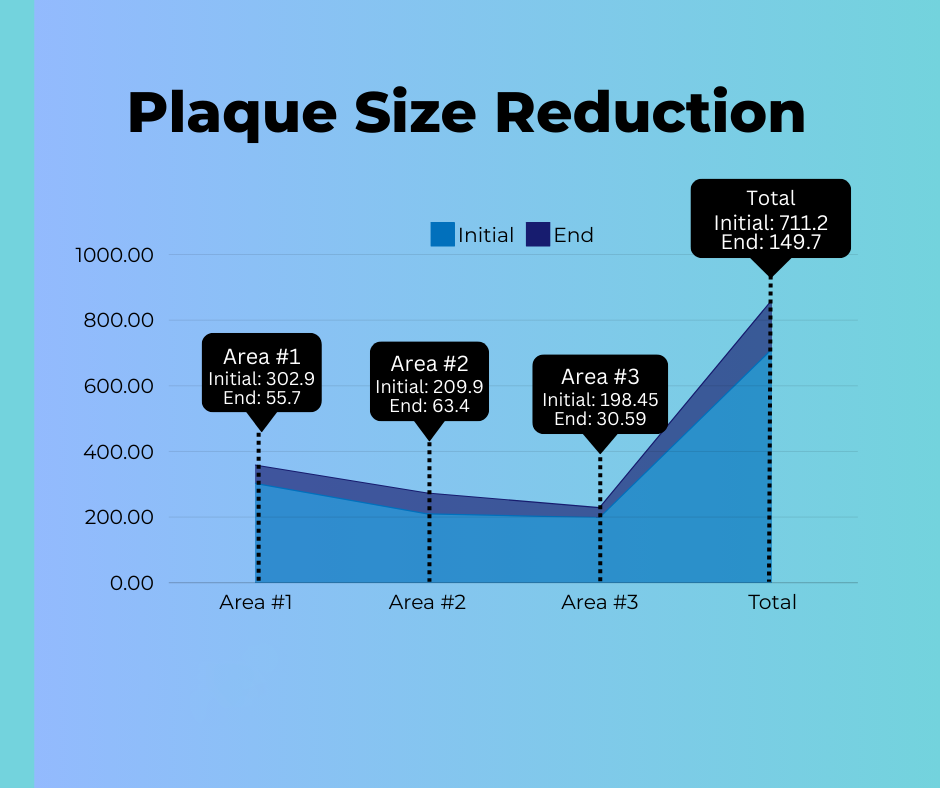

The total plaque size measured with the baseline duplex Doppler ultrasonography in Area One was 302.9 mm3 and the follow up duplex Doppler tally in Area One was 55.7 mm3, representing an 81.5% reduction in penile plaque for the 70 patients.

The average total size as measured from the baseline duplex Doppler for area two was 209.9 mm3 and the follow up results measured 63.4 mm3, representing a 70% reduction in penile plaque.

The total size as measured with the baseline duplex Doppler ultrasonography study for plaque in area three was 198.45 mm3 and the follow up duplex Doppler ultrasonography was 30.59 mm3, representing an improvement in the reduction of penile plaque of 84.6%.

Figure 2 Plaque Size Reduction

3.1 H Combined Areas Measurement:

The initial baseline plaque size total derived from duplex Doppler ultrasonography among all 70 patients in this study was 711.2 mm3. The follow up duplex Doppler ultrasonography was 149.7 mm3. The combined measurable penile plaque reduction for all areas was 79.0%.

Figure 2 Penile Plaque Size Reduction

Figure 2 Plaque Size Reduction